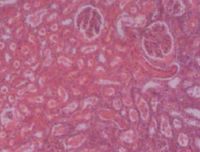

Эффективные нефропротекторы: описание и фото